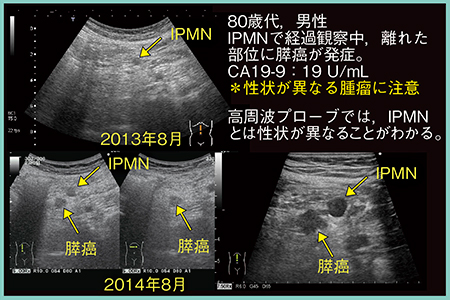

症例3は,80歳代,男性。2013年にIPMNが指摘され,経過観察中の2014年に離れた部位にIPMNの増加が認められたが,高周波プローブを用いた精査の結果IPMNとは性状が異なっており,膵癌と診断された(図9)。このように,性状の異なる囊胞には特に注意を要する。

図9 症例3:IPMNの経過観察中に発生した膵癌